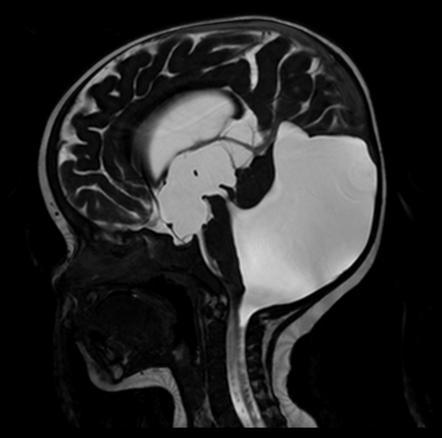

Marked obstructive hydrocephalus due to fourth ventricular outlet obstruction by fine septations

dandy walker malformation

This case illustrates a classic Dandy Walker malformation with associated aqueduct stenosis and obstructive hydrocephalus, a common associated feature

(although not part of the Dandy walker triad: